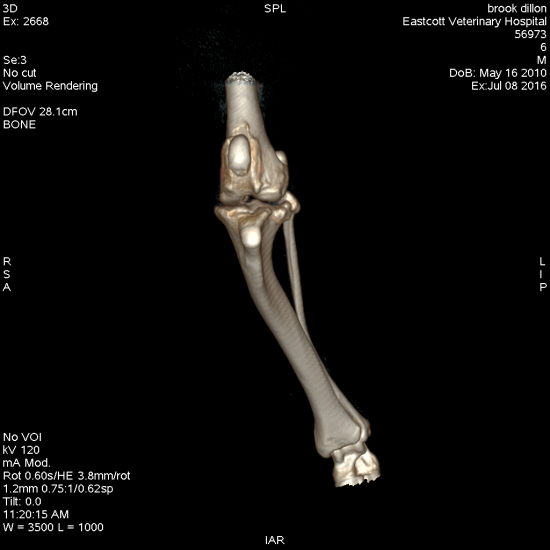

All of these can be treated effectively by adapting our standard techniques. For the cases with angular limb deformity including extreme tibial plateau angle (>34 degrees), CT of the hindlimbs allows us to perform an accurate assessment of all aspects of hindlimb alignment. This facilitates planning of the most appropriate surgery, reducing surgical time and leading to excellent clinical results.

Figure 4. Staged bilateral surgical correction of combined distal femoral varus, grade ¾ medial patellar luxation and cranial cruciate ligament rupture using distal femoral ostectomy, block recession trochleoplasty and transposed tibial plateau levelling osteotomy

Figure 5. Treatment of combined excessive tibial plateal angle (56 degrees) and severe tibial valgus deformity using a combined TPLO and cranial and medial closing wedge ostectomies